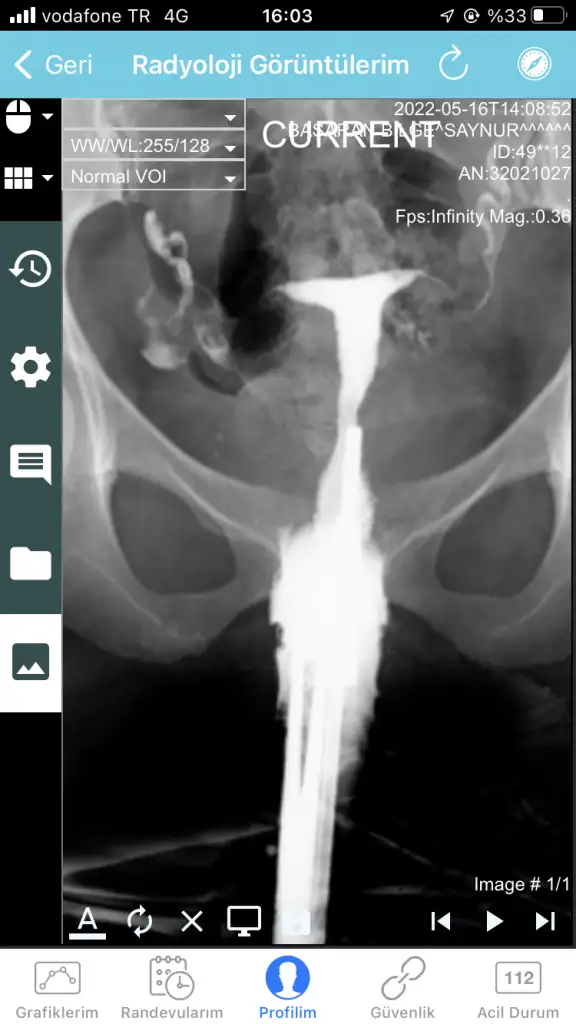

Kızlar merhaba, bugün Hsg çektirdim. Görüntülerine bakabilir misiniz tecrübeli arkadaşlar

İlk yorumu yapan olmadı mı çekimden sonra🙃 T görünümü var ama raporda şekil bozukluğu ile ilgili bir ibare yok. Ancak sol tüpün tıkalı olabilir 🤔 genel bi başlık aç istersen daha çok yazan olur inşallah ben yanlış algılamışımdır

Merhaba , tıkanıklık bu filmde açılabiliyor mu hiç bilmiyorum . Doktor yorum olarak kapalı görünüyor sanki ama ben sıvı geçişini gördüm aslında kapalı değil dedi . Anlamadım . Yani filme baktığımızda ince bir çizgi gibi geçiş var . Doktora göre de var , raporda kapalı olduğu yazıyor .